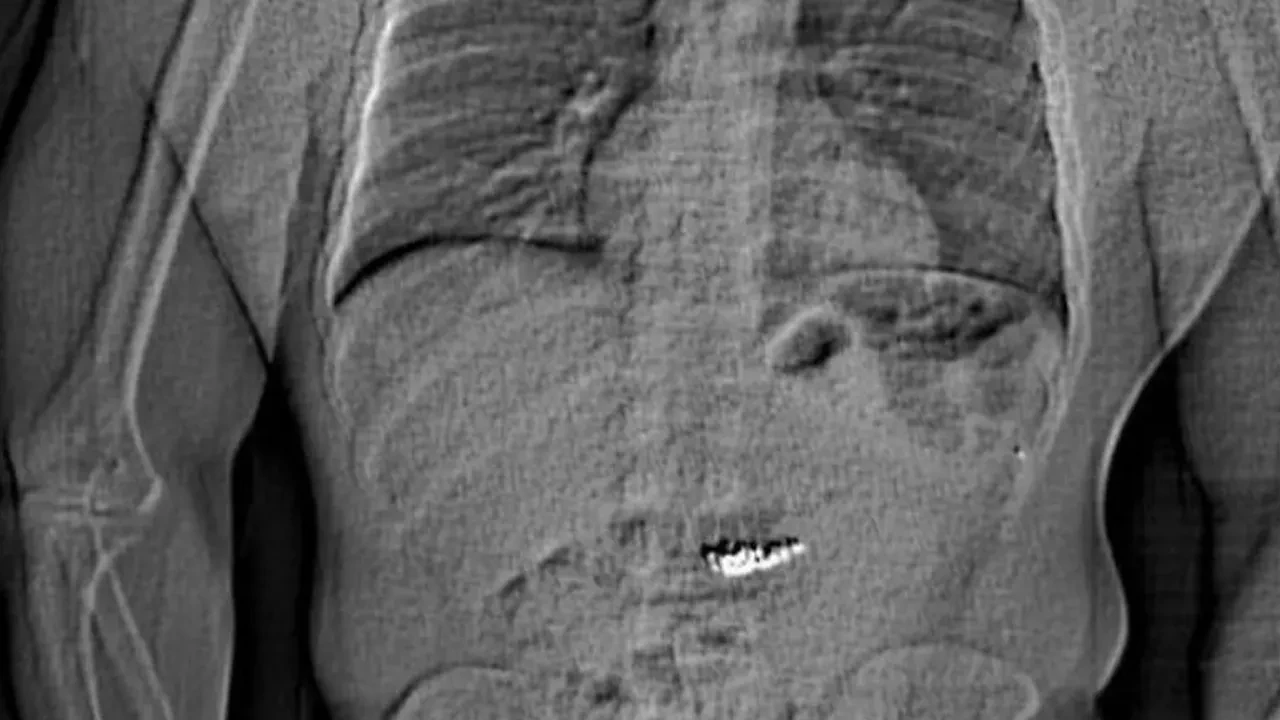

Yetkililer, Gilder’ın karnında yabancı bir cisim bulunduğunu gösteren bir röntgen görüntüsünü basına paylaştı. Ancak, mücevherlerin bulunup bulunmadığı ile ilgili herhangi bir açıklama yapılmadı. Gilder’ın geçmişte de Tiffany & Co. mağazalarına yönelik hırsızlık olaylarına karıştığı, 2022 yılında Teksas’ta benzer bir suç işlediği ve Colorado’da hakkında 48 ayrı tutuklama emri bulunduğu belirtildi.